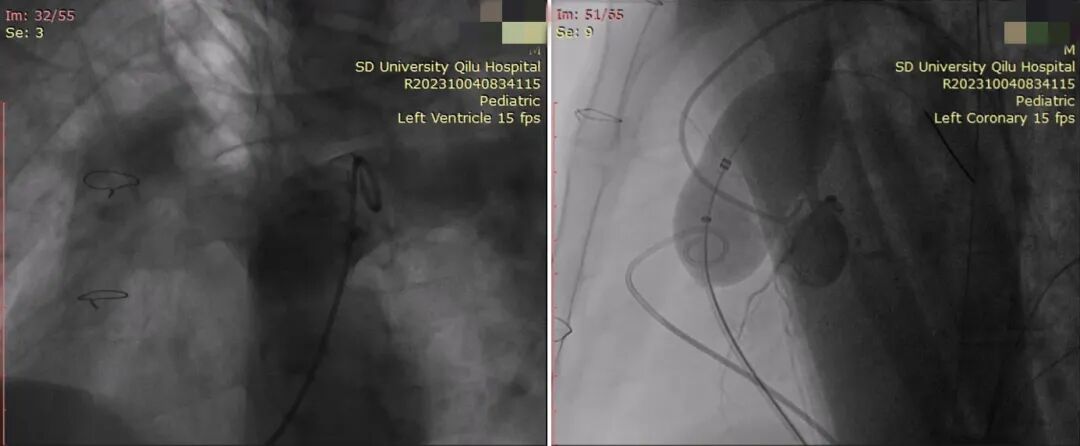

左图:肺动脉造影可见大量肺动脉瓣反流;

右图:充盈测径球囊,同时行冠脉造影